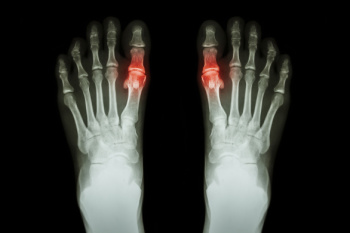

Gout, a form of inflammatory arthritis, can be excruciating, often affecting the big toe and ankles. Recognizing its symptoms is vital for timely management. The diagnosis begins with a keen observation of the symptoms, which are often sudden, intense joint pain, swelling, redness, and warmth, typically striking at night or in the early hours. The affected joint might feel tender to the touch, making even the lightest pressure unbearable. An accurate diagnosis often involves a comprehensive medical history review and a physical examination by a podiatrist. They may also conduct tests like joint fluid analysis to detect urate crystals, which are consistent with gout. Blood tests measuring uric acid levels can aid in confirmation, although high levels do not always guarantee a diagnosis. Imaging tests, such as X-rays, may reveal joint damage in chronic cases. If you have pain in the top of your foot, with a focus on the big toe, it is strongly suggested that you contact a podiatrist who can effectively treat gout.

Gout can easily be identified by redness and inflammation of the big toe and the surrounding areas of the foot. Other symptoms include extreme fatigue, joint pain, and running high fevers. Sometimes corticosteroid drugs can be prescribed to treat gout, but the best way to combat this disease is to get more exercise and eat a better diet.